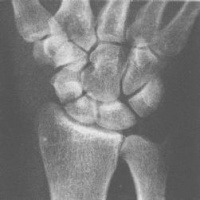

腕舟骨骨折图:http://www.mednet2000.com/yingxzd/guanjie/pic/szgz12.jpg (图片地址)腕舟骨骨折。腕舟骨中部可见透亮线。

影像学表现:舟骨骨折按骨折发生的部位分为舟骨中段骨折、近段骨折和结节部骨折。舟骨骨折的骨折线如错位不明显时,须留意下列可提示诊断的征象:①舟骨结节的骨皮质断裂;②舟骨结节部%